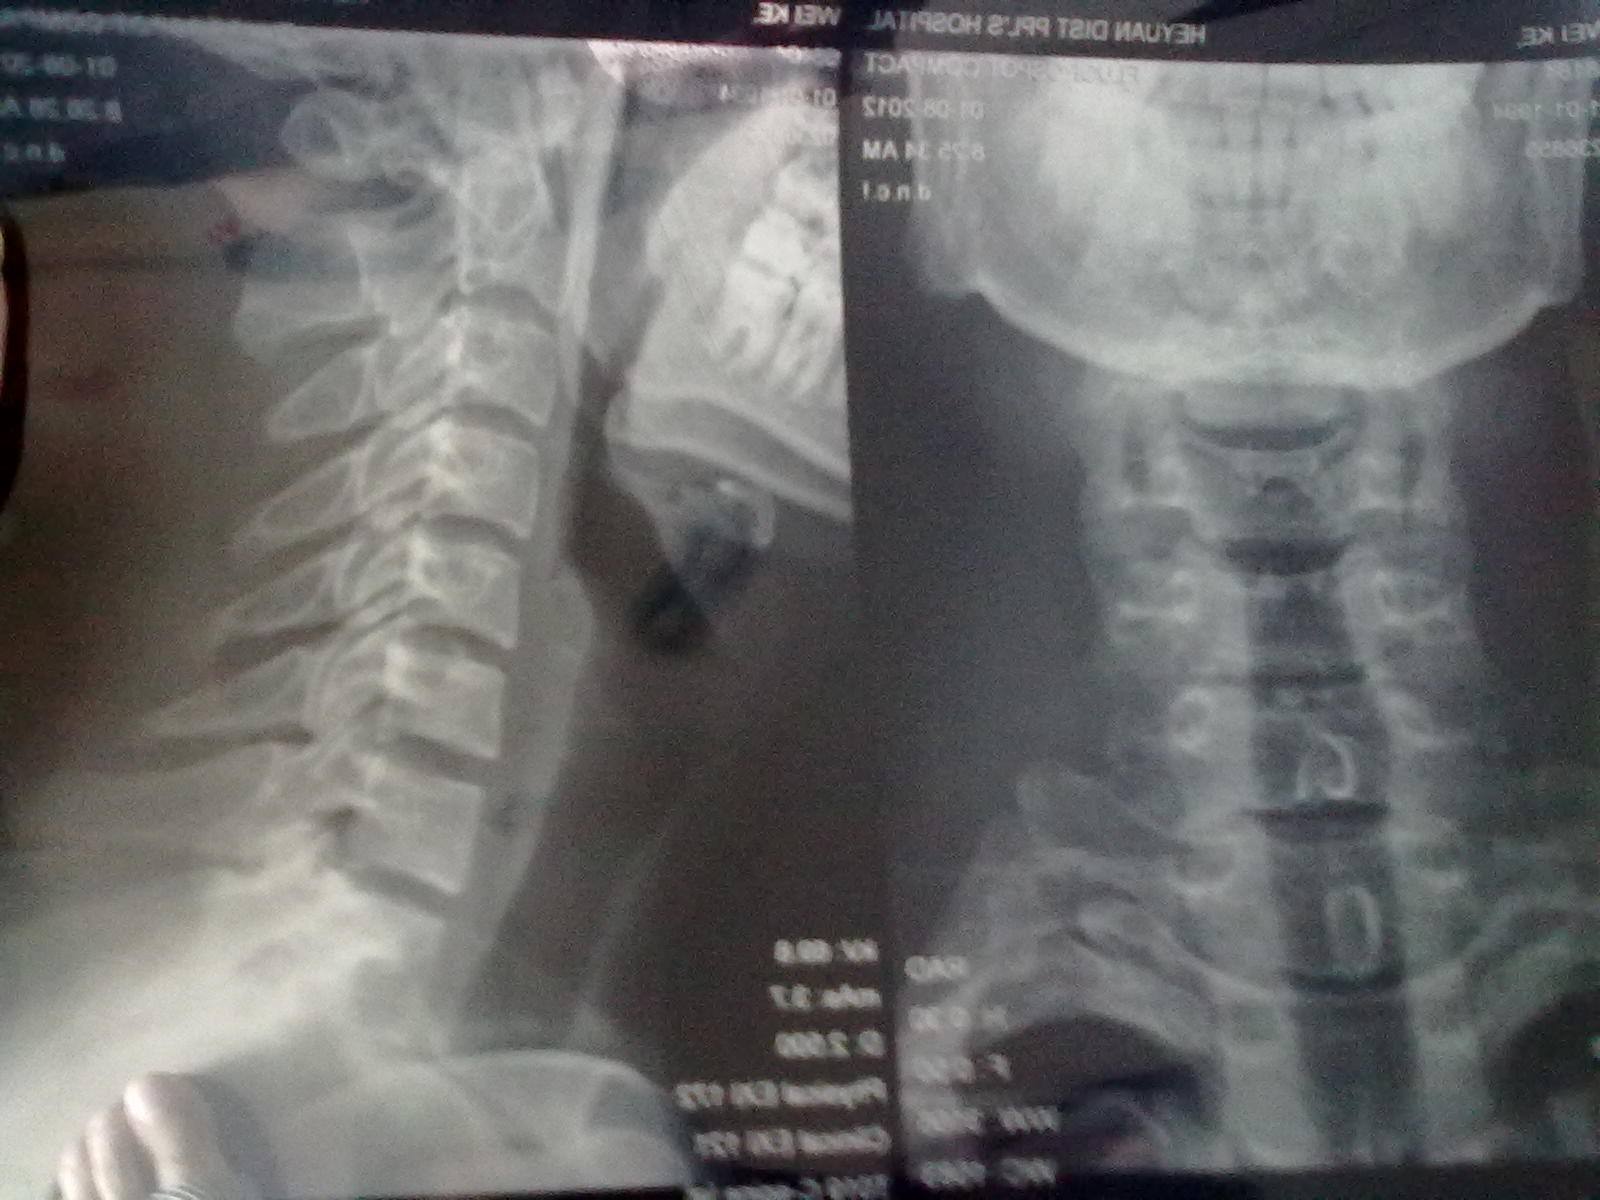

经常低头玩手机有可能会引起颈椎生理曲度变直,导致引起血压高症状!!

颈椎生理曲度变直可以引起的头晕,精神不振,高血压也可以引起类似的症状,但颈椎生理性曲度变直主要影响颈椎后侧肌肉韧带受到牵拉,劳损,两根椎动脉受到长时间牵拉,发生痉挛,导致颅底供血不足,所以颅底区域会晕晕的特别是双眉之间和额头下段,两个太阳穴,耳朵前下方,这些区域你按摩,会明显舒服好,酸胀感,这都是颅底缺血表现。